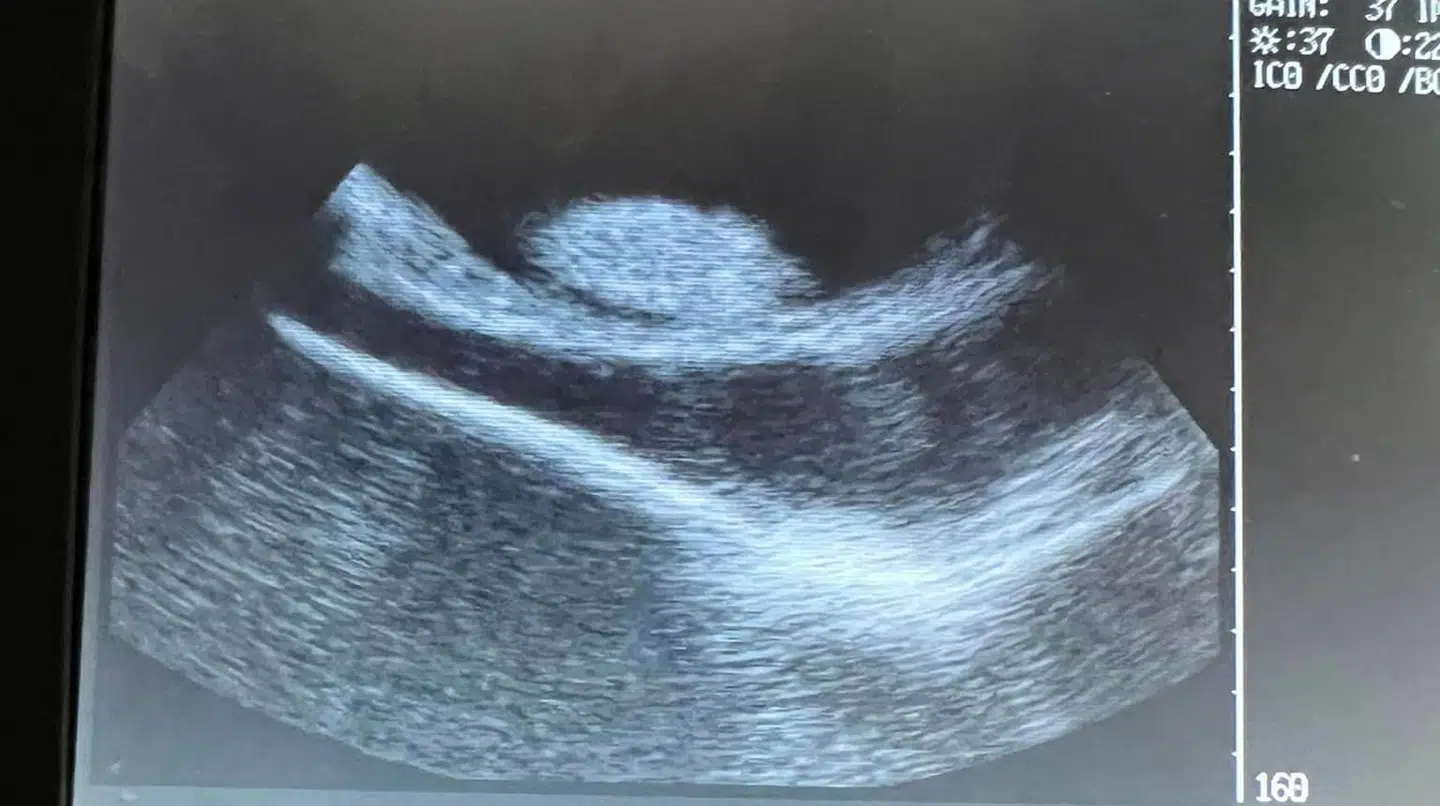

For nogle måneder siden lagde de ansatte hos Aquarium & Shark Lab by Team Ecco, der ligger i amerikanske Hendersonville, mærke til, at deres rokke Charlotte var begyndt at svulme lidt op.

Til at begynde med troede man, at der måske var tale om en tumor.

Men det viste sig i stedet, at hun var blevet gravid.